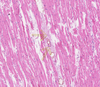

Brown Myocardial Atrophy Flashcards

Cardiac Myocytes — Lipofuscin

Dilated Blood Vessels —– Collagen Fiber